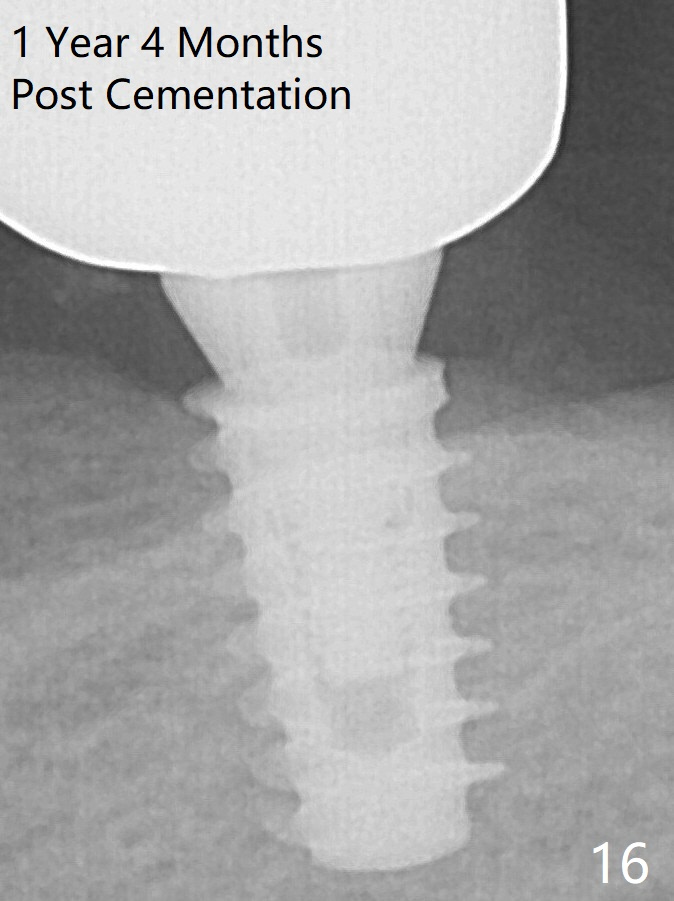

A 5x9 mm implant is placed with a pair abutment (A) to test the trajectory (Fig.6). The implant appears to have osteointegrated 2 months postop (Fig.9 with a healing abutment). There is no bone resorption 1 year 4 months post cementation (Fig.16). The implant remains stable 3.5 years post cementation (in spite of open margin), while the other abutment for the RPD (the tooth #30) has mobility with gingival recession.